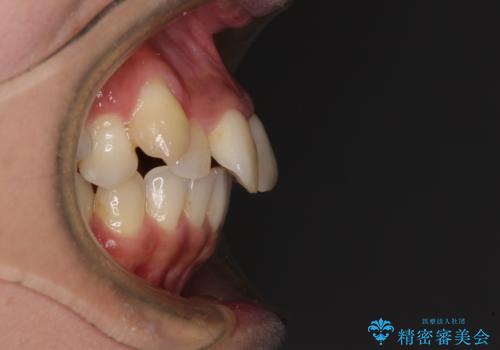

- 八重歯と上下前歯のでこぼこを気にして来院された患者様です。

上下前歯部叢生のスペース獲得のため、上下顎左右小臼歯各1歯(計4本)を抜歯して、ワイヤー装置にて矯正治療を行うこととしました。

上下の正中位置が大きくずれていたため、上下正中が合わないまま終了することが予想されましたが、思っていた以上にスムーズに歯が移動し、満足いただける仕上がりとなりました。